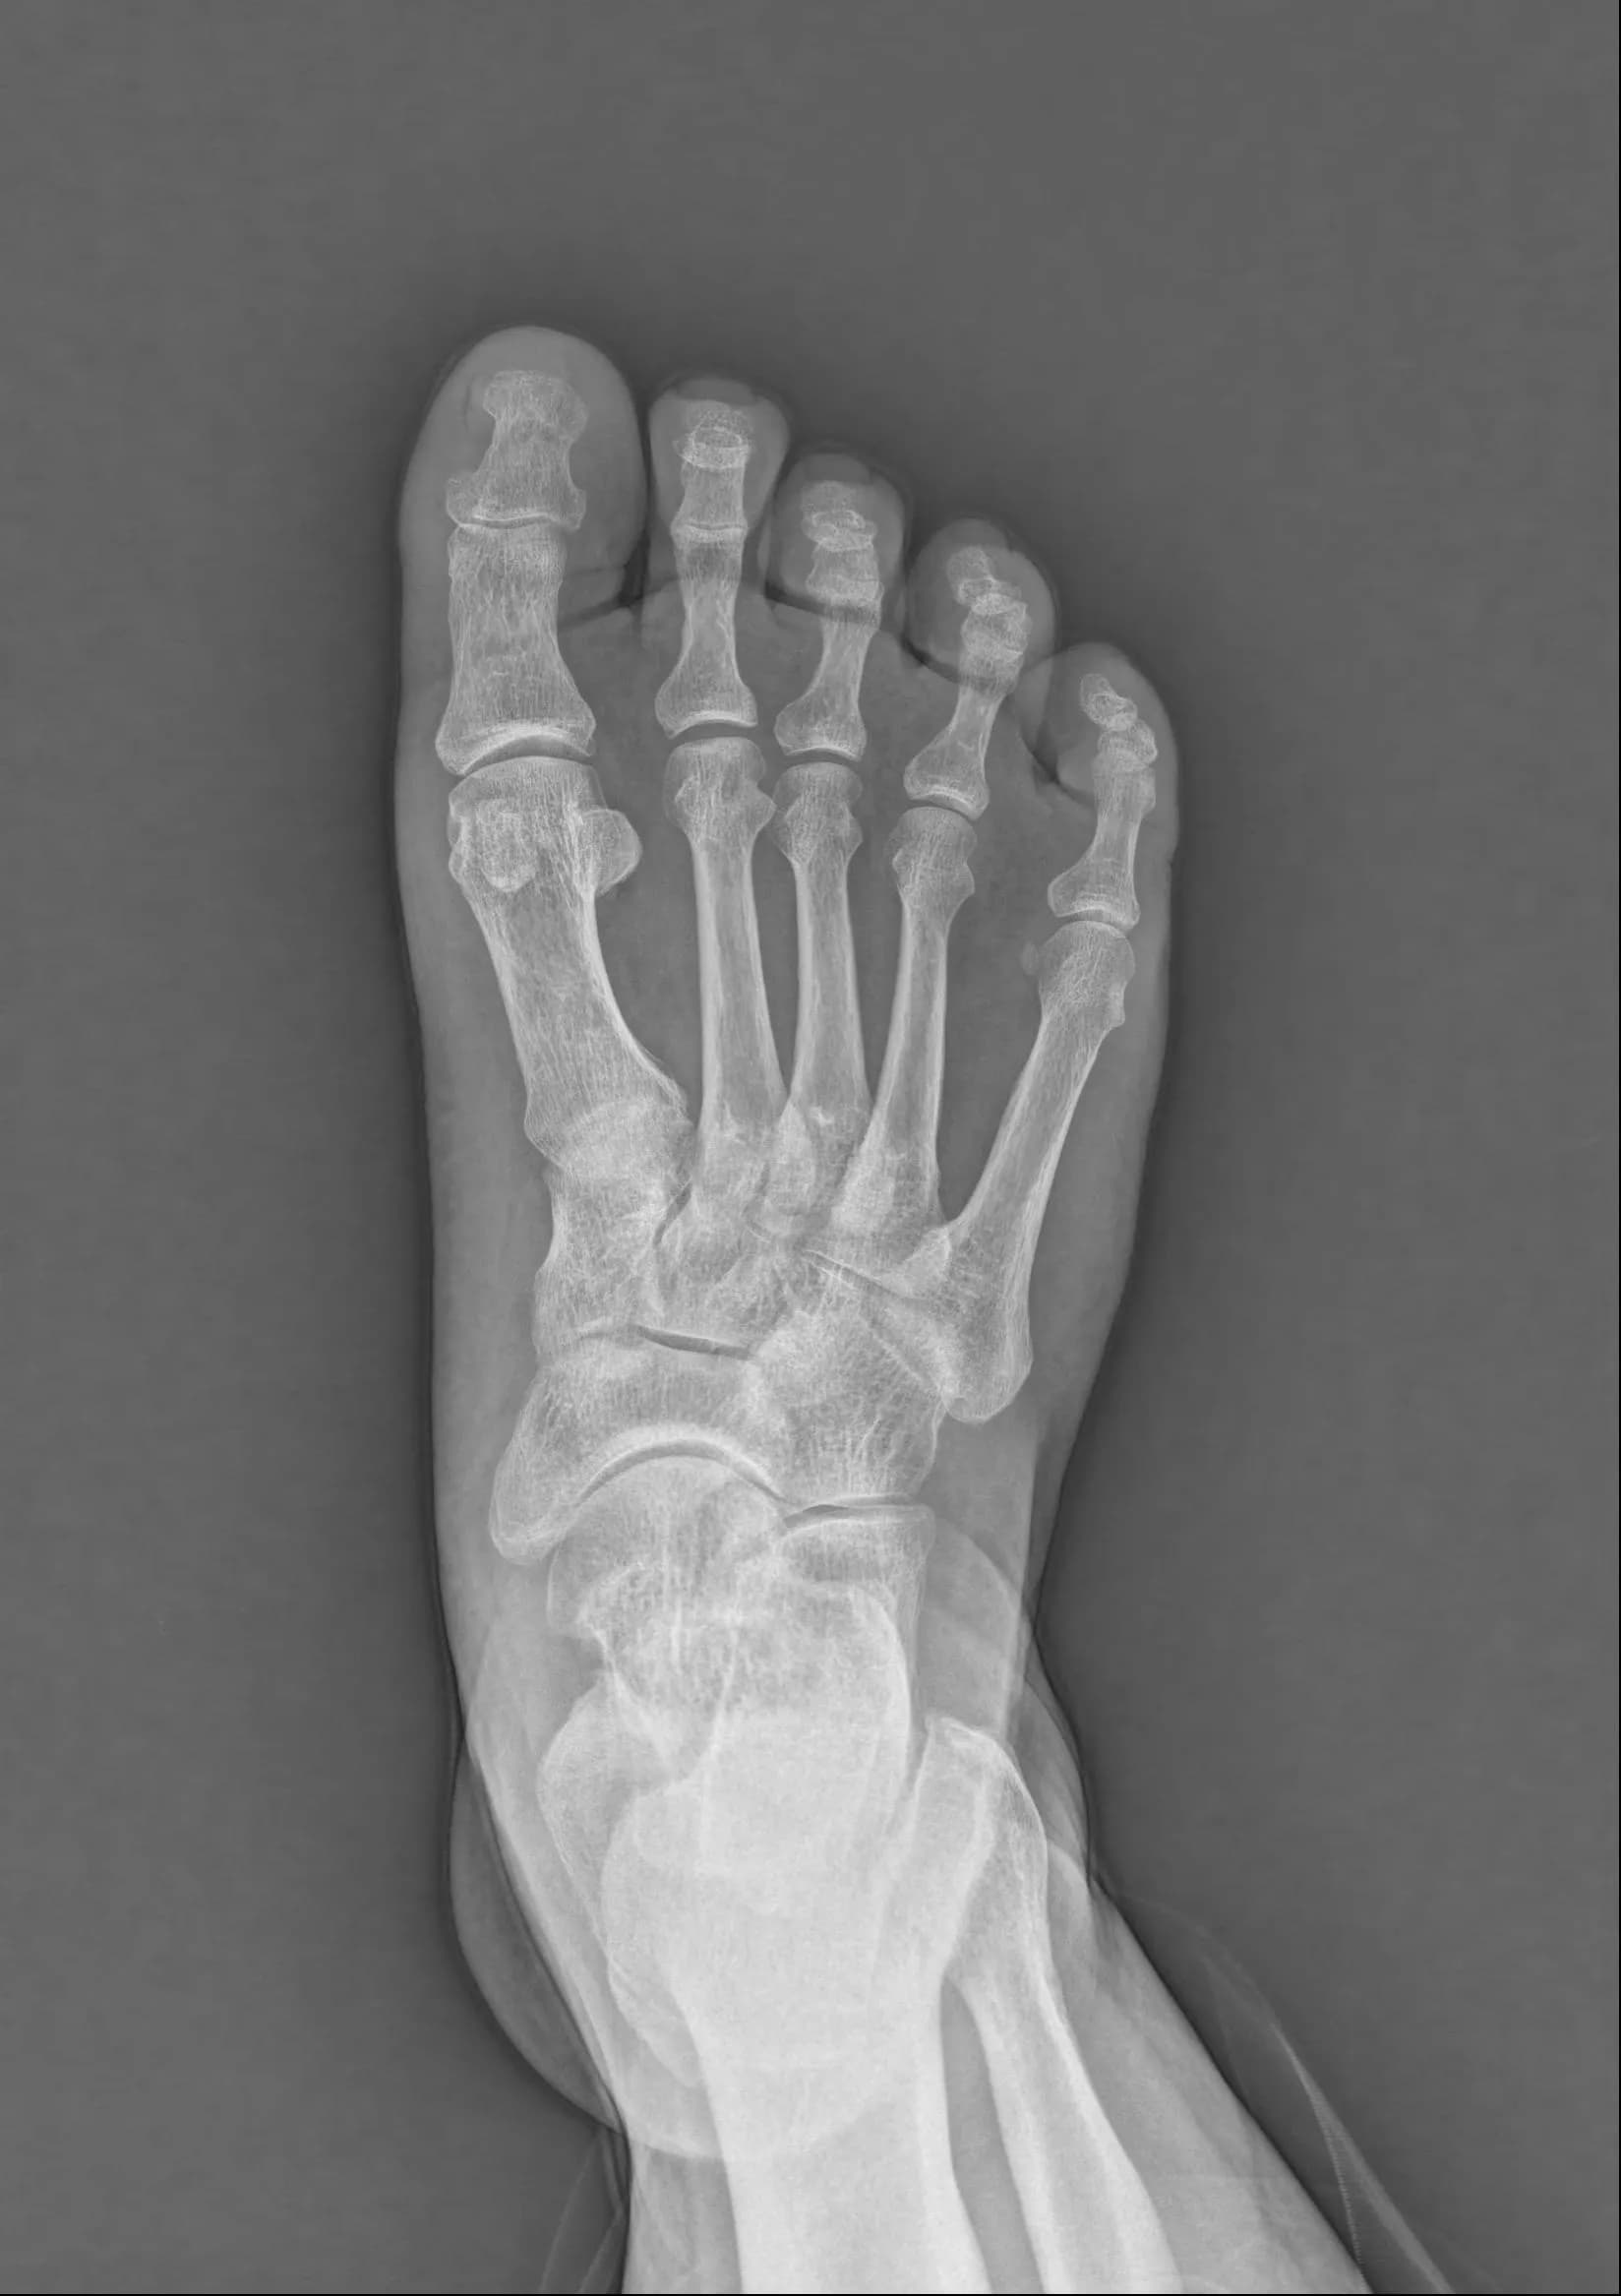

Musculoskeletal X-ray AI Analysis

부위를 클릭하여 결과 이미지를 확인하실 수 있습니다.